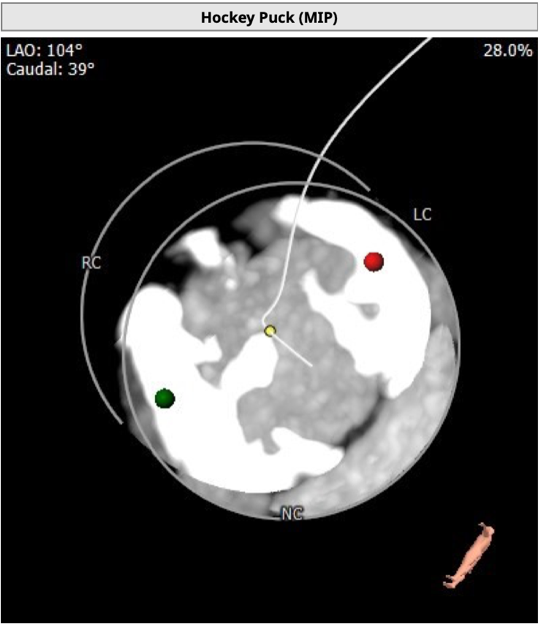

主动脉根部评估

CT 数据显示该患者为二叶式主动脉瓣

LVOT 周长74.6mm,周长径23.8mm;

SOV 28.7mm*33.8mm;

STJ 短径29.9mm,长径31.6mm;

瓣叶增厚,重度钙化,1075HU:1762mm³;

瓣环水平夹角48度。

左冠开口高度14.2mm,右冠开口高度18.4mm,左右冠脉高度可。